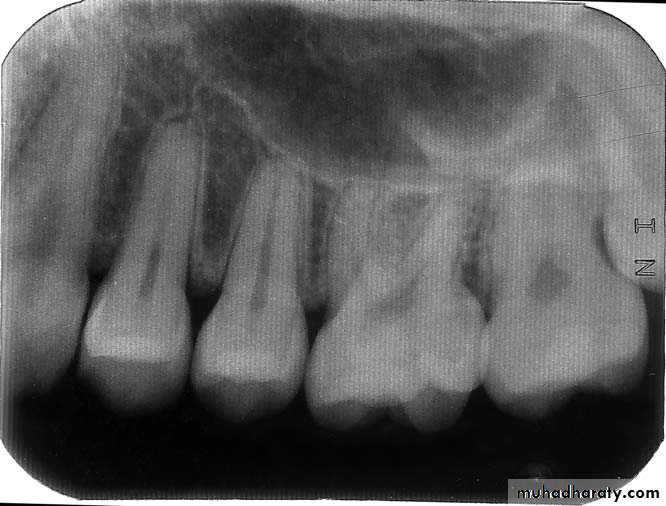

Initial view of the nonrestored tooth 24.Periapical radiograph of left maxillary premolars. No significant findings were present .

Bite test using a wooden wedge revealed pain in tooth 24.A crack was observed under transillumination . On the occlusal surface of tooth 24, from a mesial to distal orientation.

A stainless steel orthodontic band was cemented to confirm the diagnosis. The patient could bite without pain after this procedure.A cone beam computed tomography showing the crack in

a mesial-distal direction, involving the mesial, occlusal, and distal faces.Cracked tooth